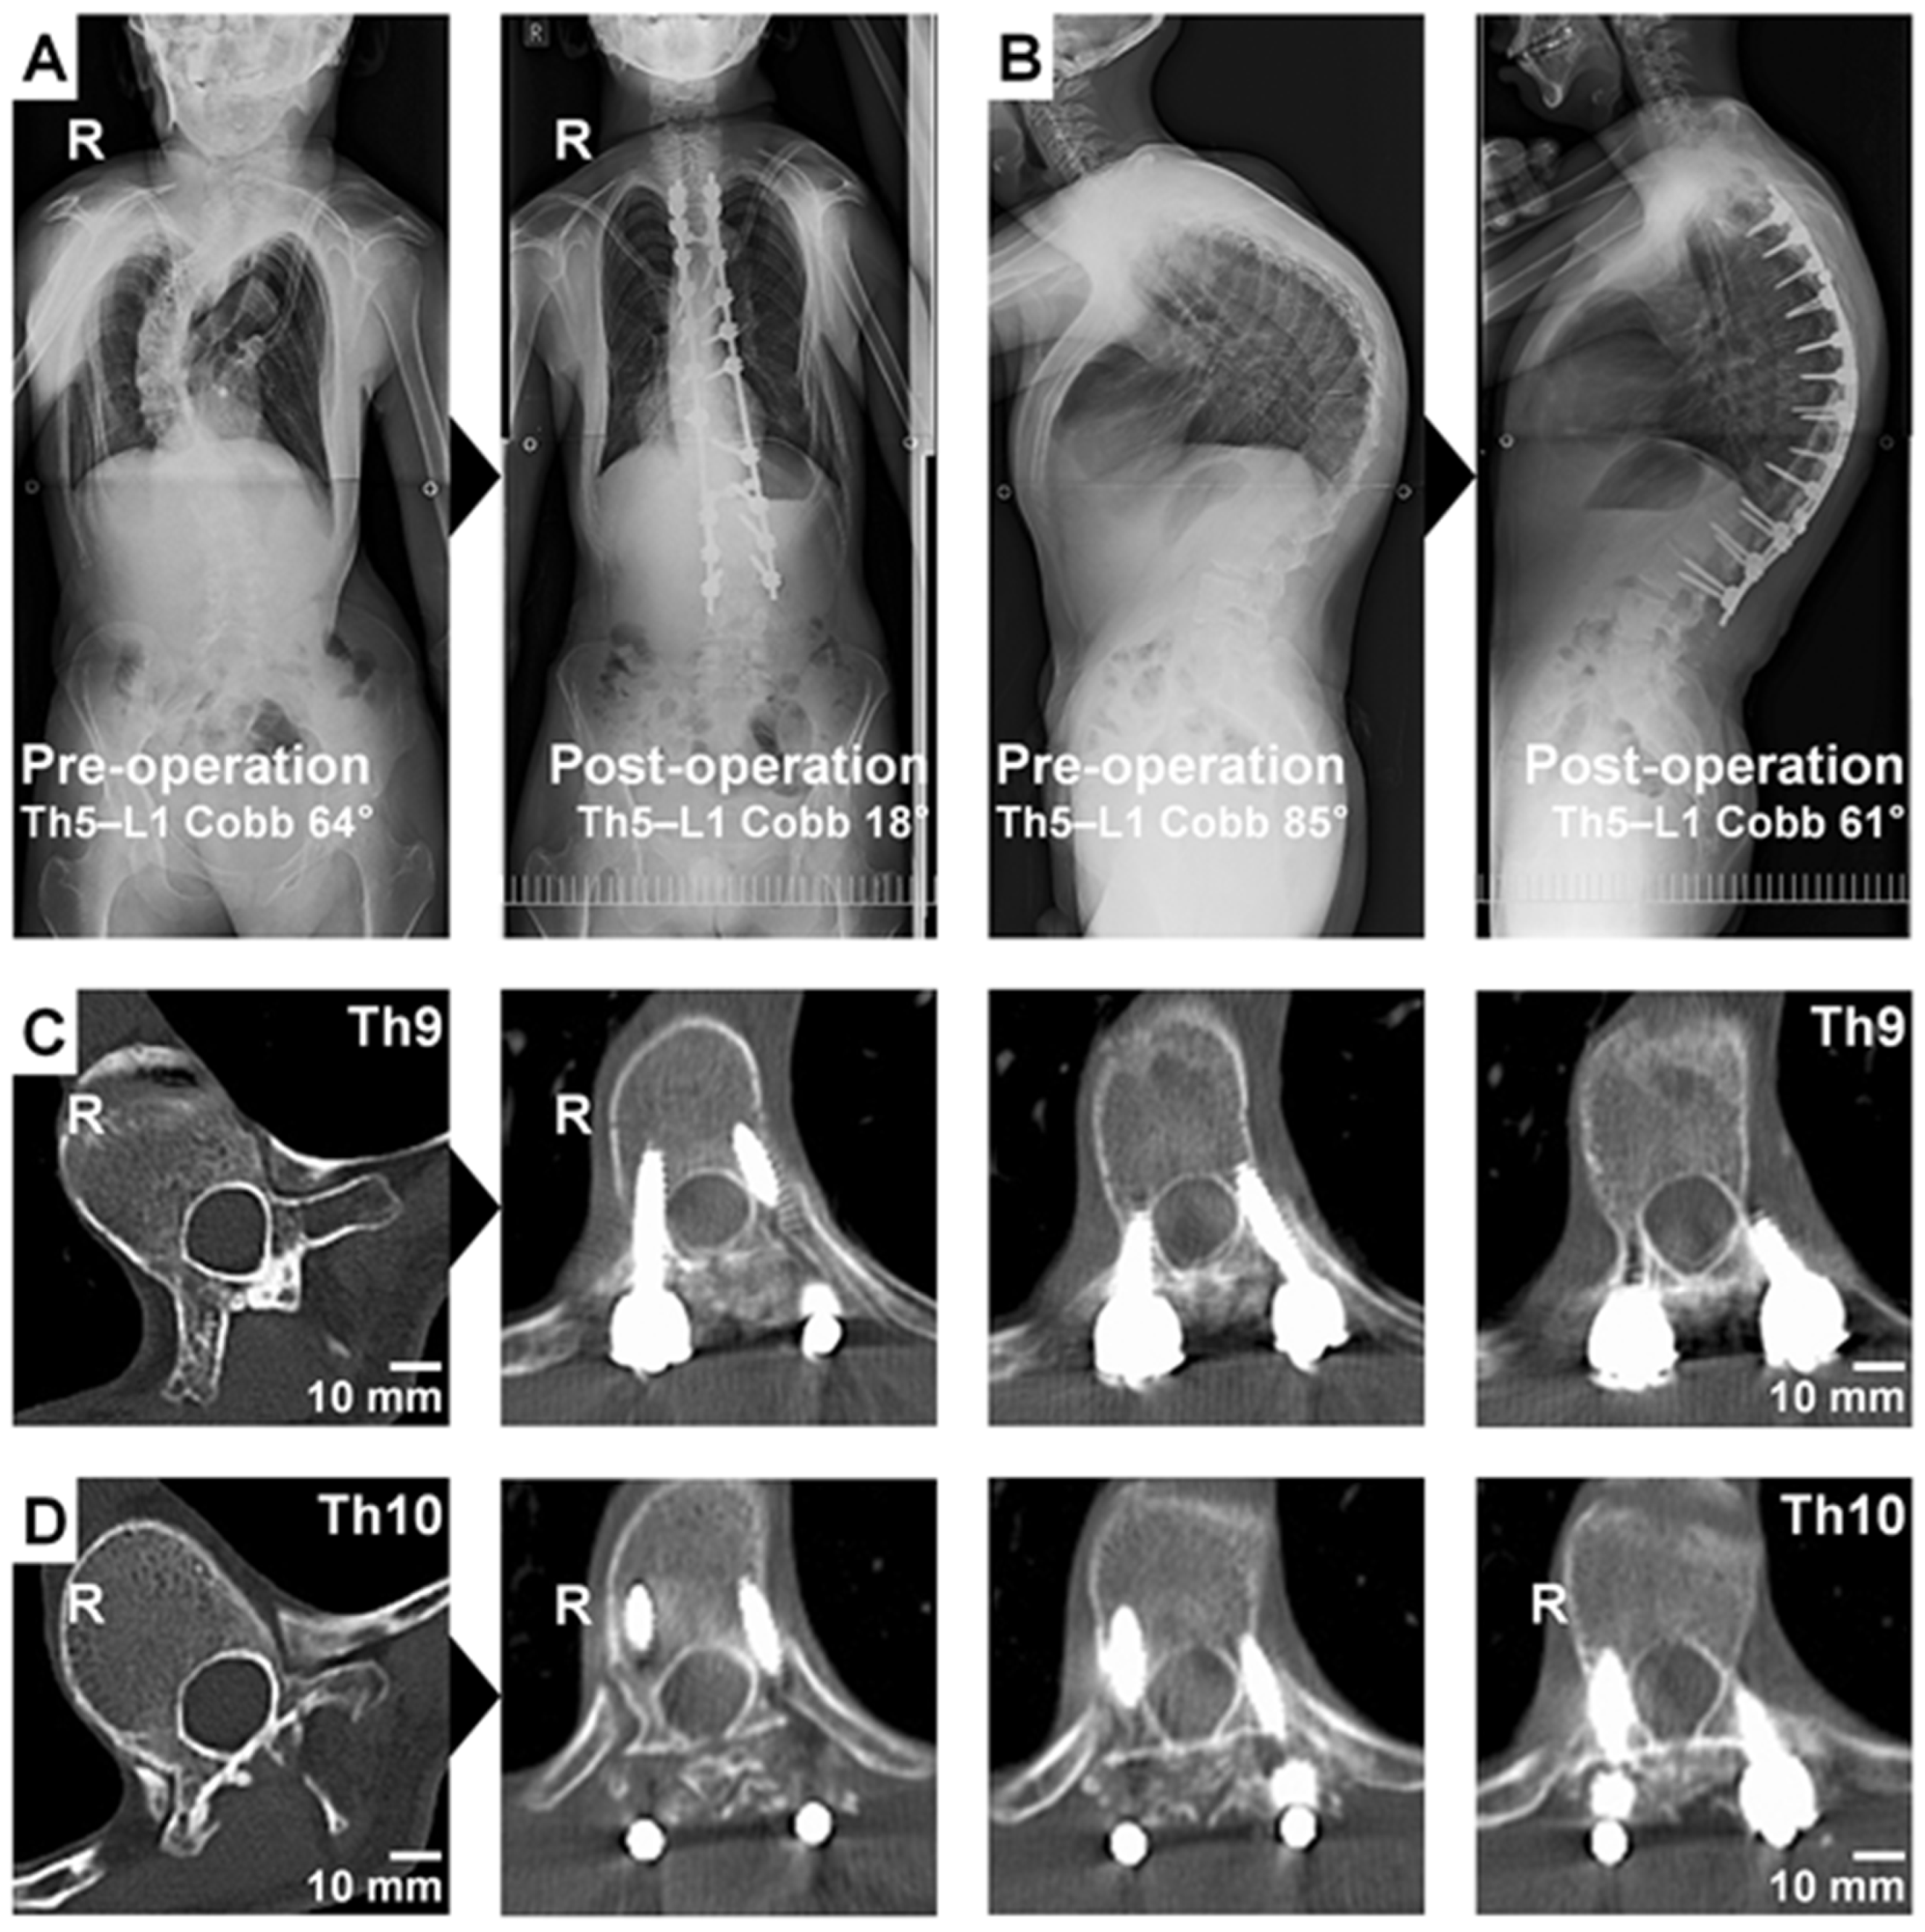

A 20-year-old man with the Sotos syndrome presented at pre-operation right-curved scoliosis with the Cobb angle of 64° and severe kyphosis with the Cobb angle of 85° at Th5–L1 (Figure 2A,B). We performed posterior segmental fixation surgery at Th4–L3 with the aid of the ECD probe with a curved tip. In this patient, left concave side’s pedicles at Th9 (Figure 2C) and Th10 (Figure 2D), the apical vertebrae of scoliosis, was remarkably narrowed because of the severe deformity. The ECD probe’s guidance of audio alerts and light-emitting diode warning signals was useful for safe pedicle screw placement without any violation of the spinal canal. First, the ECD signal was medium in the pitch and cadence when the curved tip toward the lateral position was within the posterior pedicle’s cancellous bone. Then, the signal became higher (but not as high as the medial wall perforation) when the curved tip toward the lateral position was possibly located outside the pedicle at the intermediate depth calculated by preoperative CT. Finally, when the curved tip turned toward the medial position and went forward to the intra-vertebral body’s cancellous bone, the signal became low to medium again. Specifically, the ECD signal could help surgeons estimate the depth, direction, and position of the probe tip, e.g., by rotating, which does not require any extra effort to alter their technique for pedicle screw placement. At post-operation, his right-curved scoliosis and kyphosis at Th5–L1 were treated up to 18° and 61°, respectively (Figure 2A,B). Consequently, in-out-in insertion of pedicle screws with the retention of the medial wall of left Th9 and Th10 pedicles was accomplished (Figure 2C,D).

Figure 2.

A technical note of a probe with an electrical conductivity-measuring device (ECD) in a 20-year-old man with the Sotos syndrome and scoliosis. (A,B) Anteroposterior (A) and lateral (B) whole spine radiographs at pre-operation and post-operation. His right-curved scoliosis and kyphosis at Th5–L1 were surgically treated. (C,D) Axial CT images at pre-operation and post-operation. The diameter of left concave side’s pedicles at Th9 (C) and Th10 (D), the apical vertebrae of scoliosis, was severely reduced because of the deformity. The ECD probe was useful to place pedicle screws safely without perforation of the medial wall of left Th9 and Th10 pedicles. Consequently, in-out-in pedicle screw insertion was accomplished at the left side of both segments under the ECD guidance of audio alerts and light-emitting diode warning signals. In all images, R indicates the right side of the body.